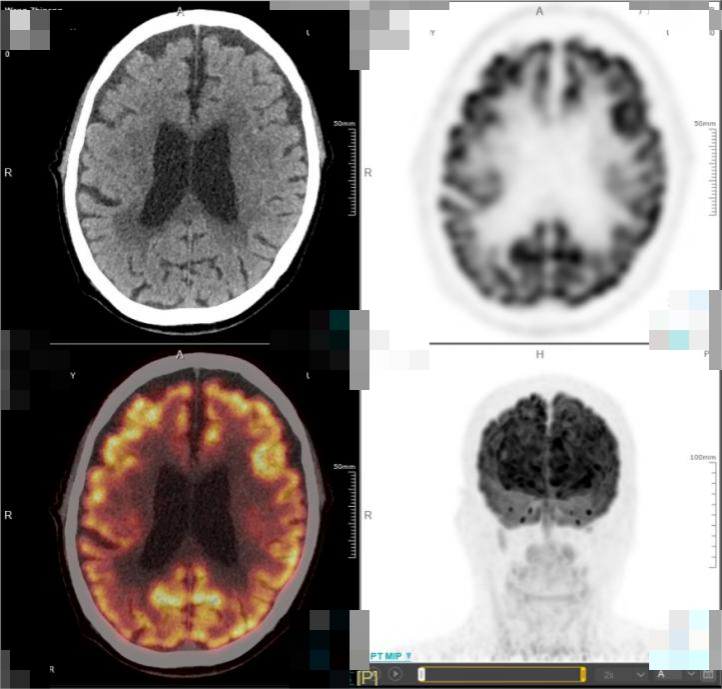

· 2025年5月,外院进行的头颅MRI检查结果显示,该患者的肿瘤再次进展。基于患者目前的疾病情况,中心医生先对其行全脑放疗,使用BTK抑制剂口服治疗,并且同步准备CAR-T细胞培养。此外,该患者还接受了氟达拉滨联合环磷酰胺方案进行预处理治疗,并于6月26日成功回输CD19 CAR-T细胞。在放疗后,患者的头颅MRI提示颅内病灶较前明显减少、减小。而CAR-T细胞治疗后50天复查PET-CT显示,患者的颅内肿瘤病灶已完全消失,达到完全代谢缓解(CMR)

图4.png图2. 患者 PET-CT结果(CAR-T细胞治疗后50天)